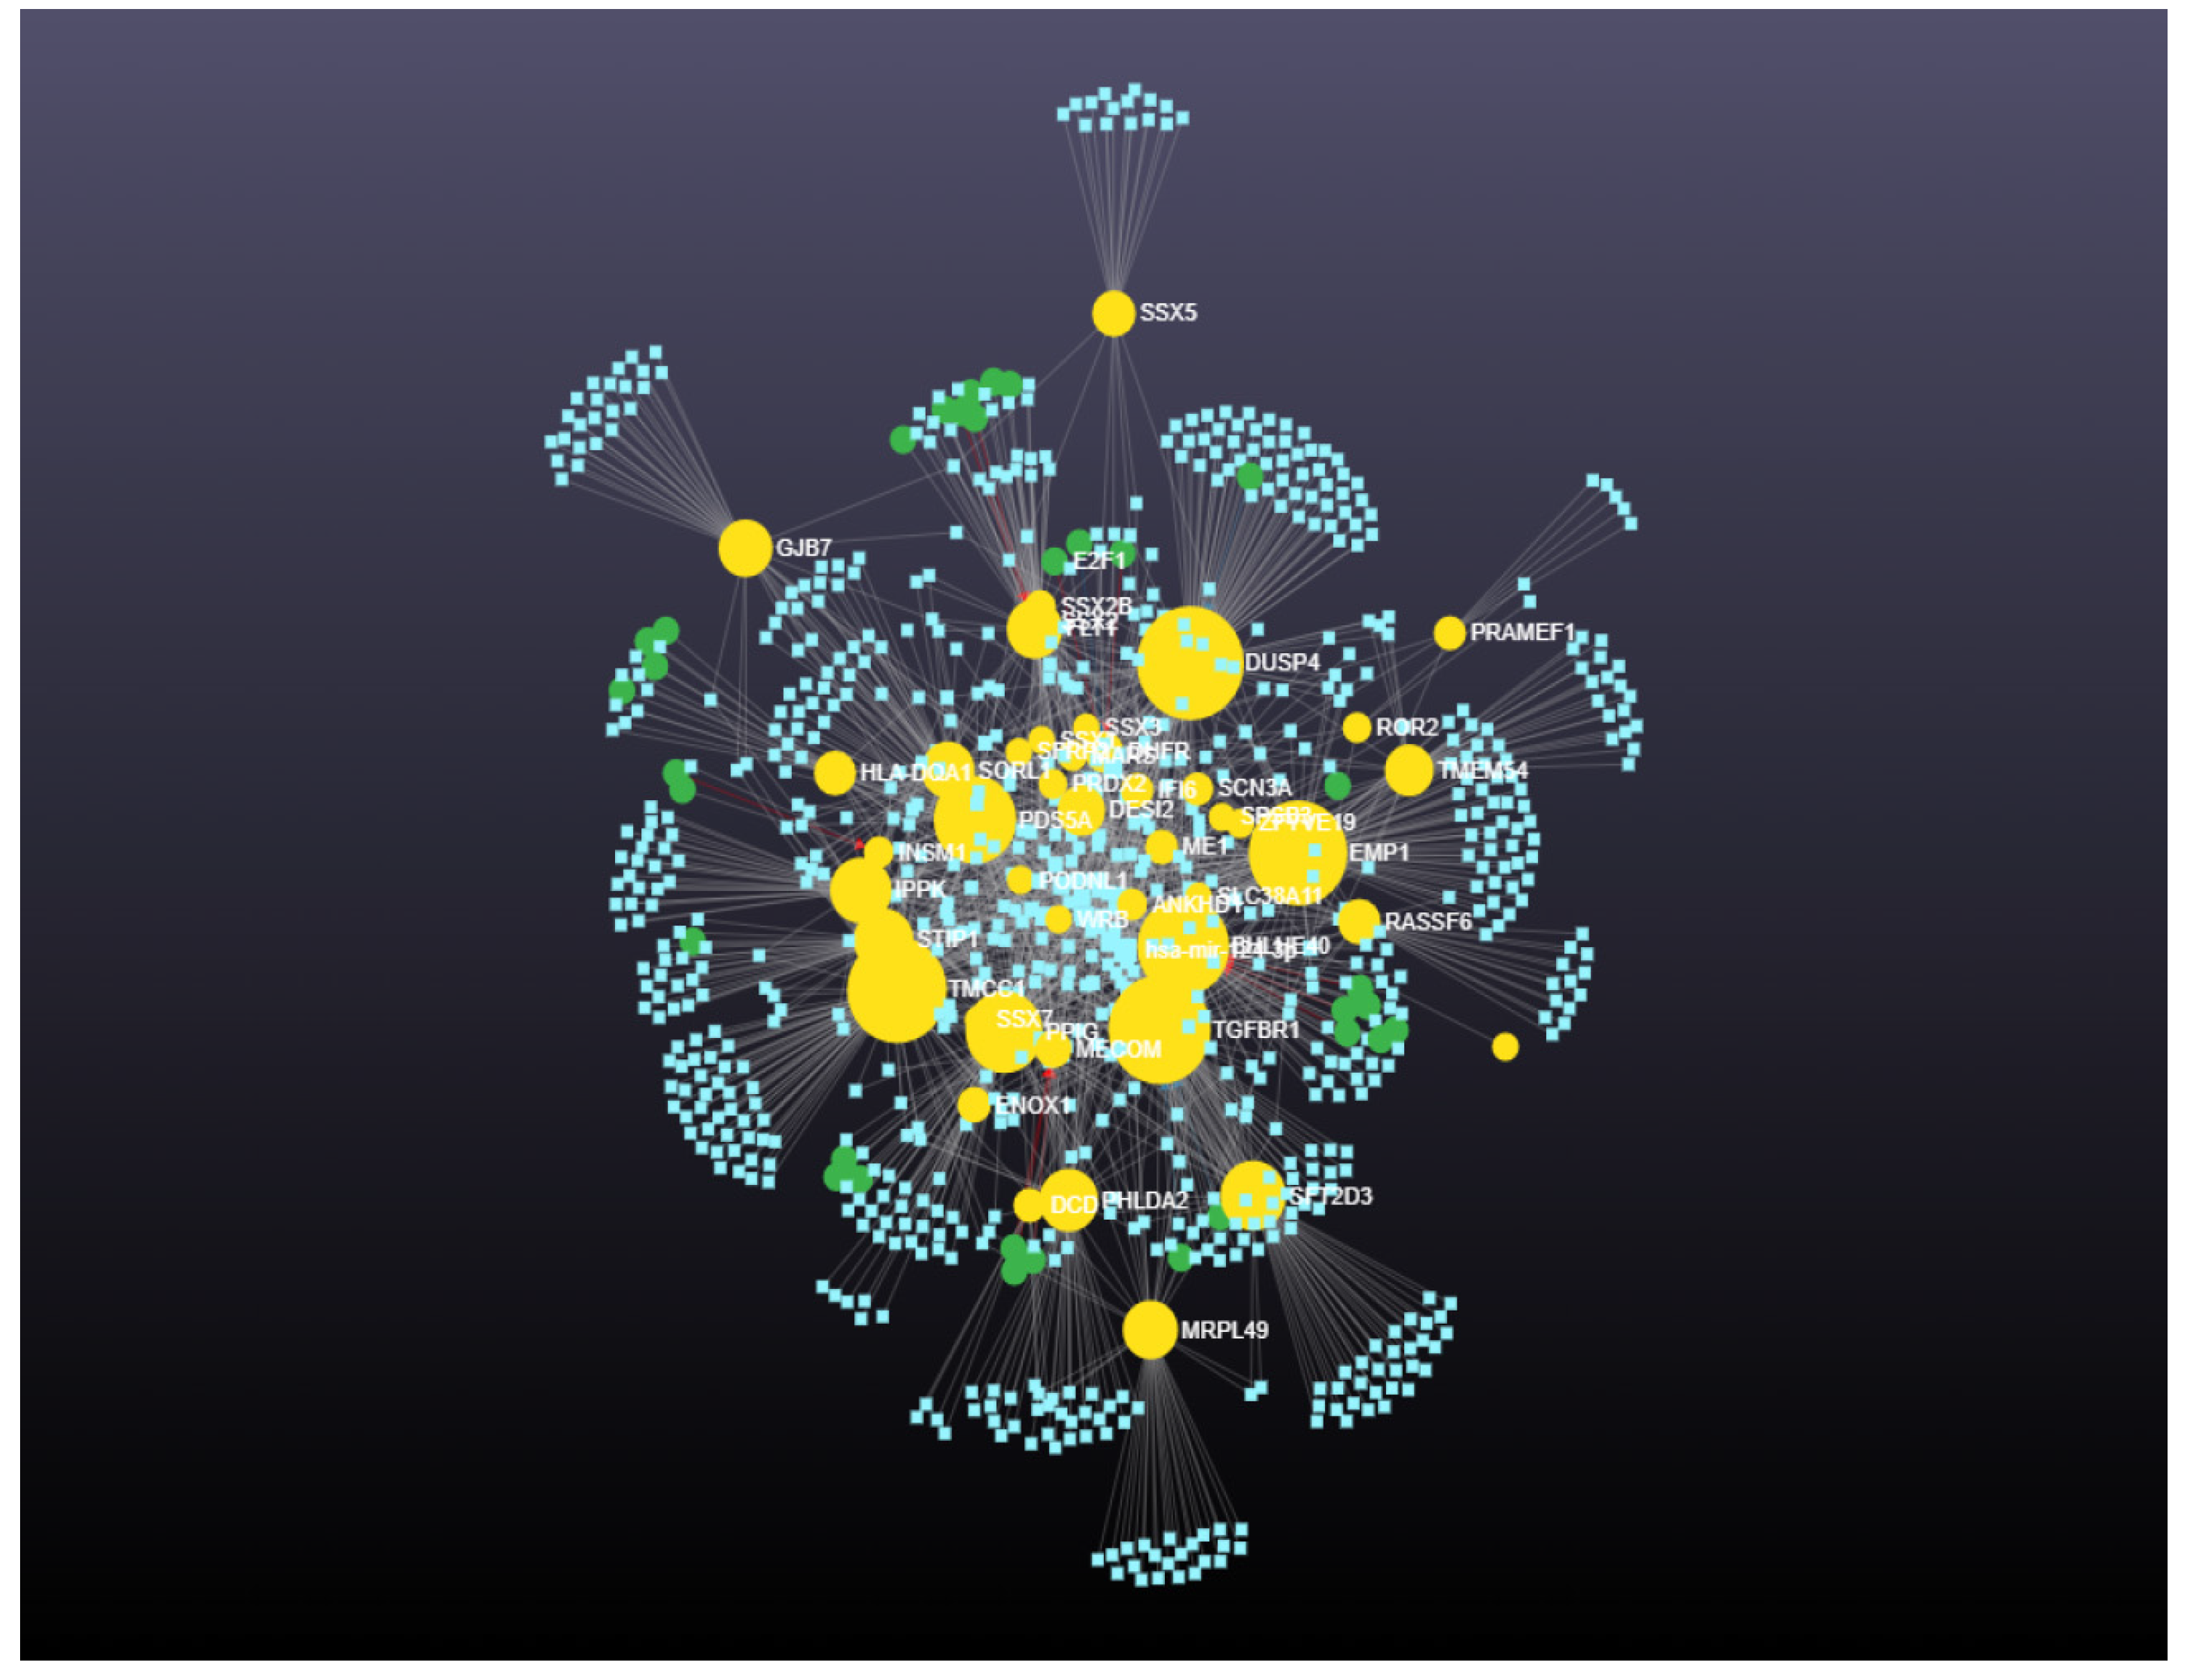

2.4.1. Prediction and Analysis of Differentially Expressed Genes

3. Results

4. Discussion

4.1. Upregulated Genes with High Betweenness

4.2. Downregulated Genes with High Betweenness Centrality